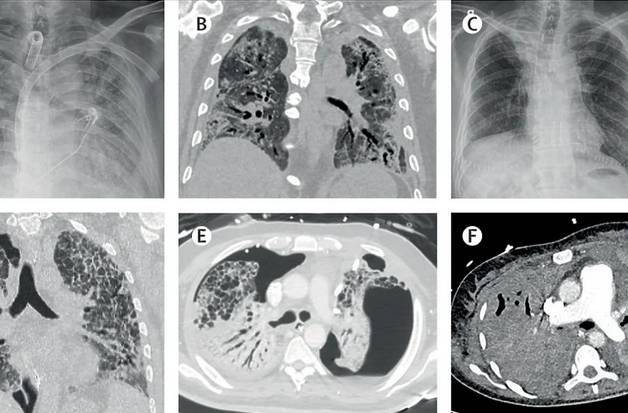

Klinika za hirurgiju Medicinskog univerziteta i Opća bolnica u Beču sakupili su sva dosadašnja iskustva o transplantaciji pluća kod pacijenata oboljelih od COVID-a 19 u svijetu i razvili opće kriterije za transplantaciju ovog organa.

Bečki program transplantacije pluća je u međunarodnom konzorciju stručnjaka iz SAD-a, Evrope i Azije vodeći u svijetu. Do sada je prema bečkom programu uspješno provedeno 40 transplantacija pluća kod COVID pacijenata u svijetu, a na Medicinskom univerzitetu u Beču 12.

Četrdesetčetverogodišnja Bečlijka je u maju 2020. godine bila prva pacijentica u Evropi kojoj je nakon teške kliničke slike COVID-om i potpunog otkazivanja pluća urađena transplantacija pluća. U momentu transplantacije PCR test je pokazao postojanje virusnih čestica, ali one nisu smatrane zaraznim.

Za transplantaciju moraju biti ispunjeni slijedeći kriteriji: iscrpljenost svih konzervativnih opcija terapije, izostanak oporavka pluća oštećenih COVID-om 19 unatoč četverosedmičnoj terapiji podrške disanju putem ECMO (izvantjelesna membranska oksigenacija) aparata, potvrda o uznapredovalom i nepovratnom oštećenju oba plućna krila u nekoliko uzastopnih pregleda CT aparatom, starost ispod 65 godina i nepostojanje relevantnih popratnih oboljenja.